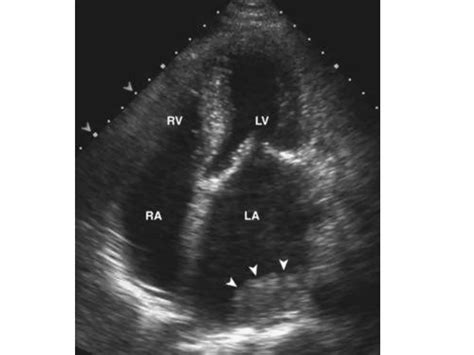

Left Atrial Size: The size of the left atrium is evaluated. In mitral stenosis, the left atrium often enlarges due to the increased pressure.

Pulmonary Artery Pressure: Elevated pulmonary artery pressure can indicate the presence of pulmonary hypertension, a common complication of mitral stenosis.